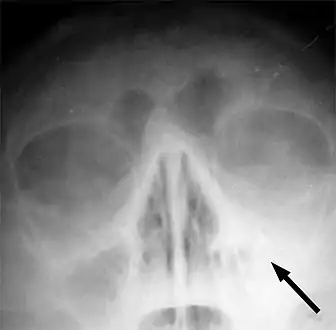

Imaging by either X-ray, CT or MRI is generally not recommended unless complications develop.[54] Pain caused by sinusitis is sometimes confused for pain caused by pulpitis (toothache) of the maxillary teeth, and vice versa. Classically, the increased pain when tilting the head forwards separates sinusitis from pulpitis.

X-ray of left-sided maxillary sinusitis marked by an arrow. There is lack of the air transparency indicating fluid in contrast to the other side.